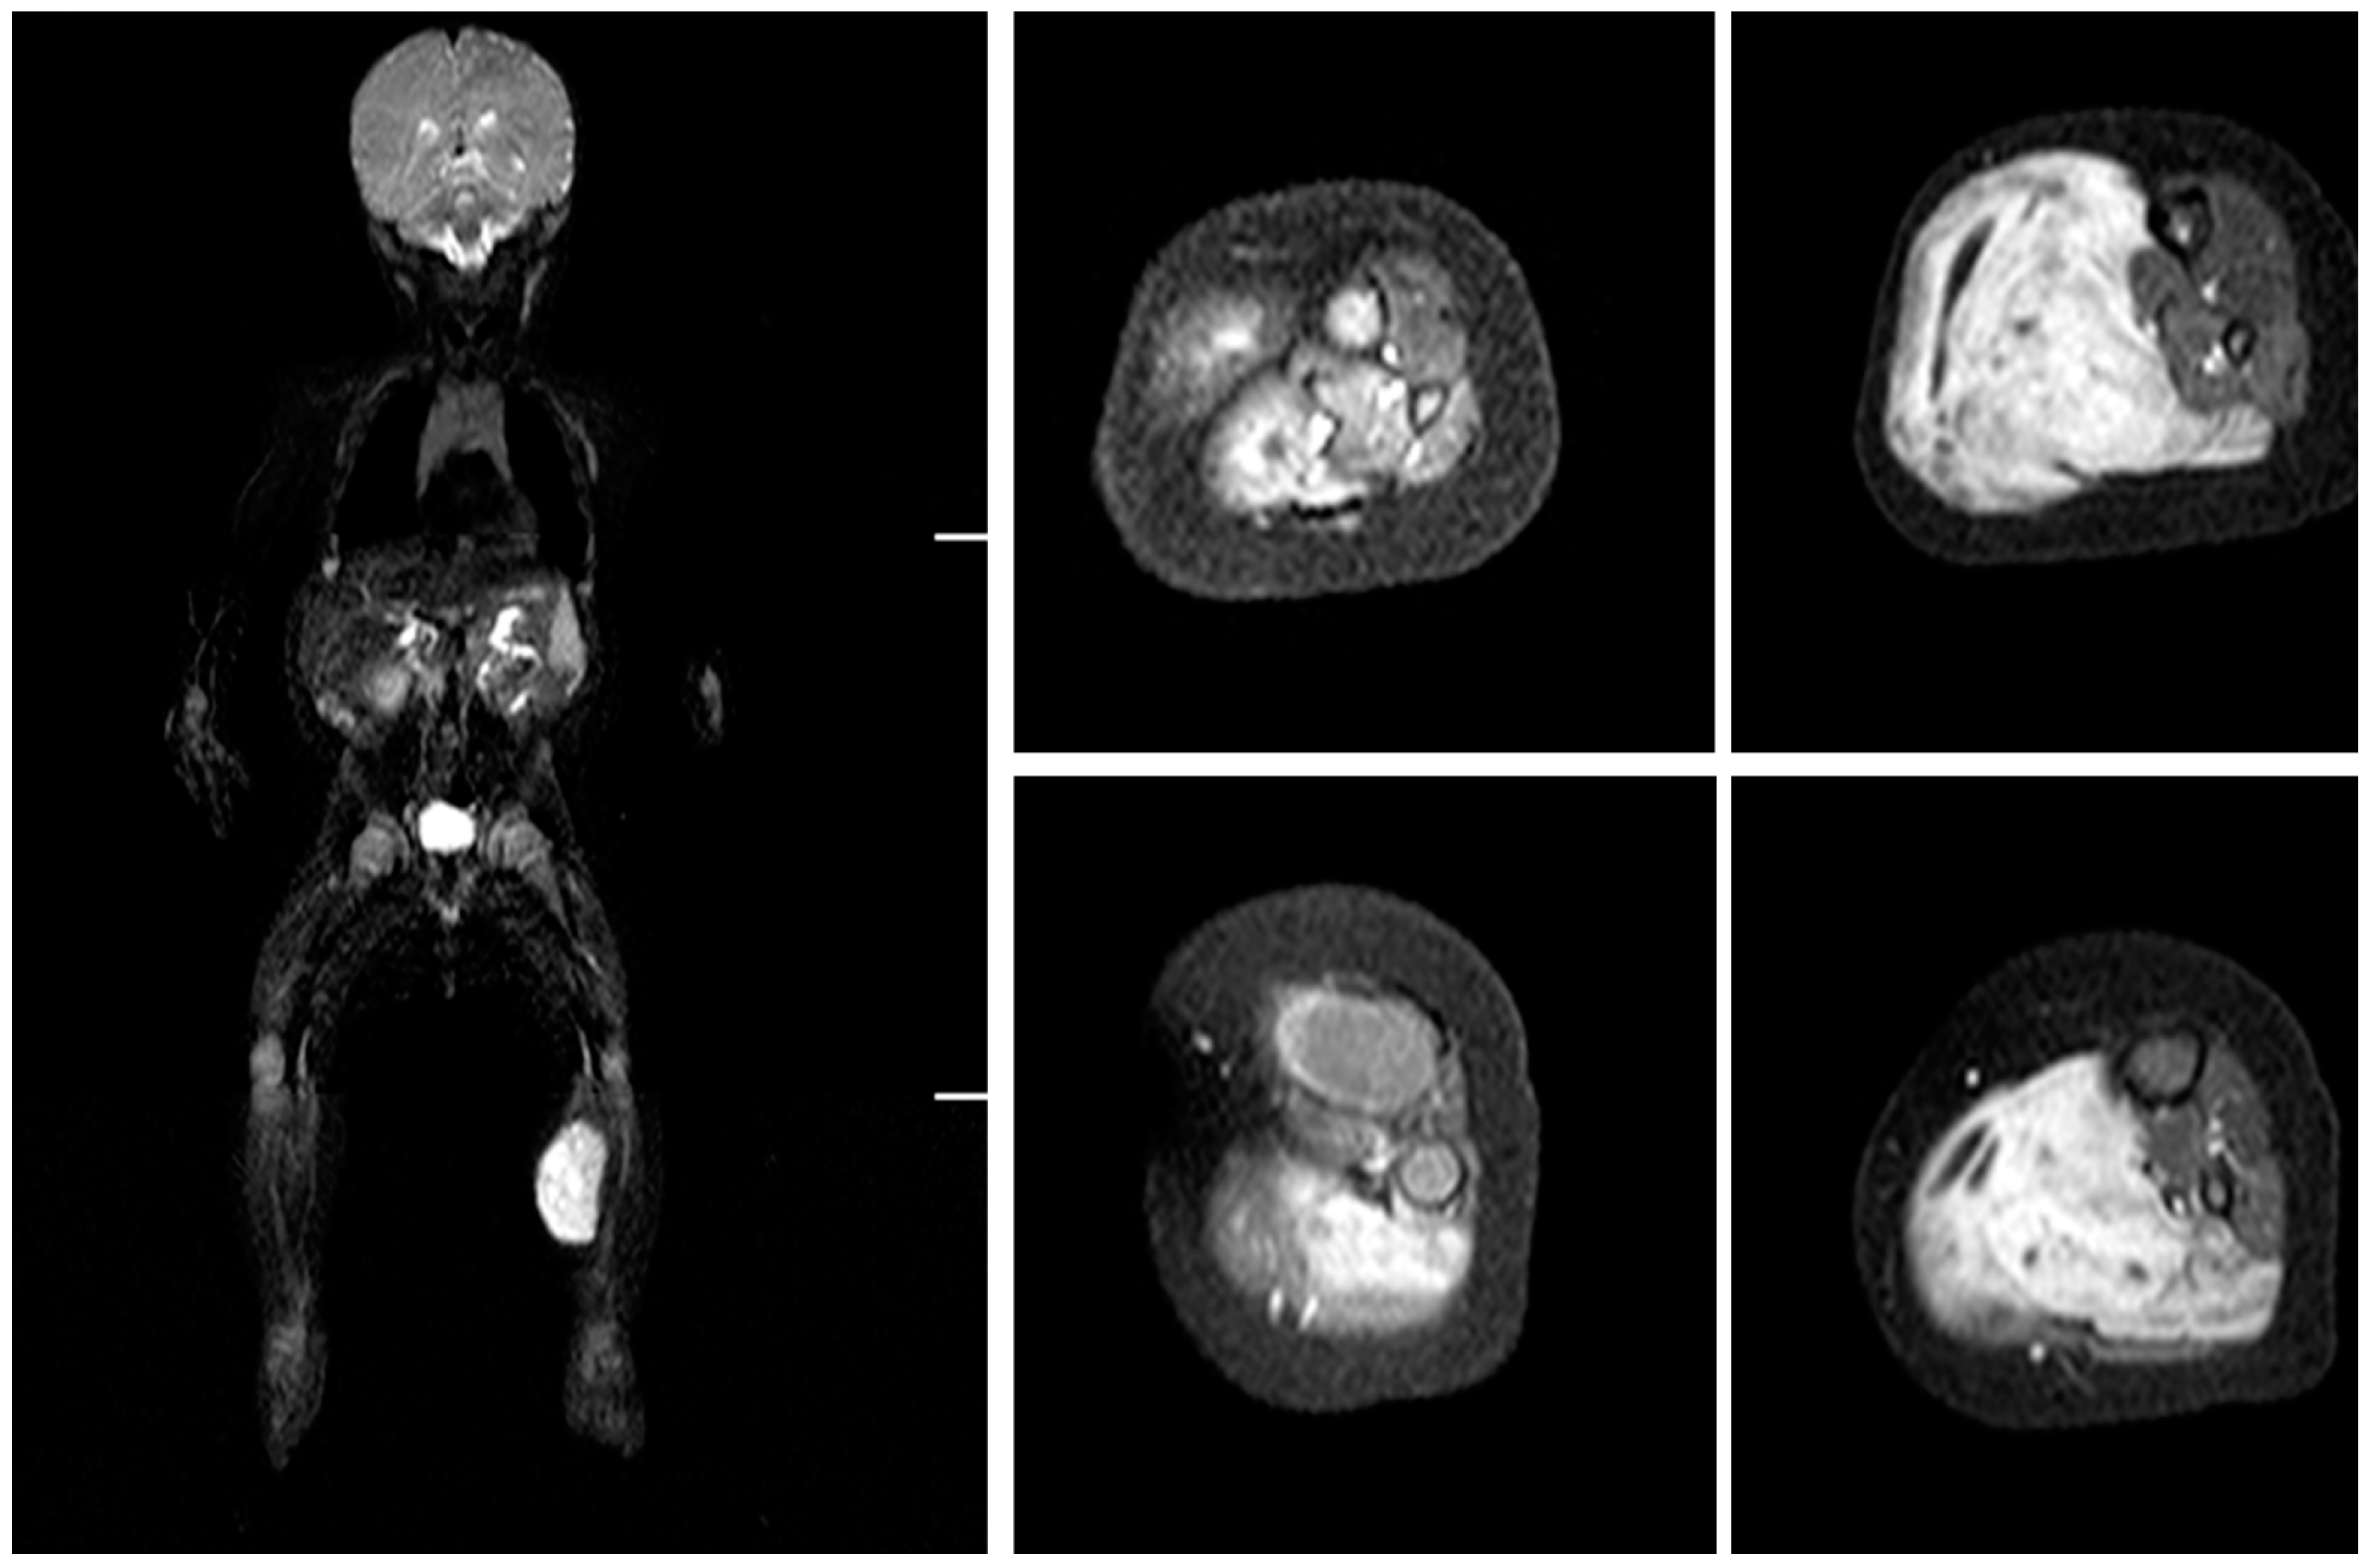

During the postoperative period, no tumor recurrence or metastases were observed. At the two-year follow-up, the patient’s left side was visibly smaller than the right, however, he performed all lower leg movements without hindrances (Figure 4). The Medical Research Council’s scale (MRC scale) was used to evaluate muscle power of the limb. The MRC scale of posterior compartment muscle strength for the movement of the talocrural joint scored 4–5 points as strength was little bit lower in comparison to the healthy side. The MRC for quadriceps muscle for the movement of knee joint scored 5 points as there were no differences with healthy side. Lateral compartment muscles MRC for movement of talocrural joint scored 5 points and deep posterior compartment muscles MRC scored 5 points for toe flexion. Sensation innervation at the peroneal and tibial nerve zones of the foot were intact and the patient reacted to the pain using a two-point discriminatory test. Decreased sensation was found at the lateral part of the foot and lateral malleolar side. Range of motion (ROM) of the knee joint flexion 0–140° (reconstructed) and contralateral 0–145°, ankle joint plantar flexion 0–40° and dorsiflexion 0–20° (reconstructed), and the contralateral ankle joint plantar flexion 0–45° and dorsiflexion 0–20°. LEFS (Lower Extremity Functional Scale) was 92.5% as he still is not allowed to enter the bath by himself and FAOS (Foot and Ankle Outcome Score) was 99%. The patient’s physical development is on track with other children his age (Supplementary Video S1). There is a great prognosis as control diagnostics have not shown any new tumors or distant masses (Figure 5).

Figure 5. Magnetic resonance imaging (MRI) at the two years follow up. Reconstructed superficial compartment with functional vastus muscle flap can be visualized and no RMS (rhabdomyosarcoma) recurrence present. The healthy right size approximately 30% bigger comparing reconstructed triceps muscles.